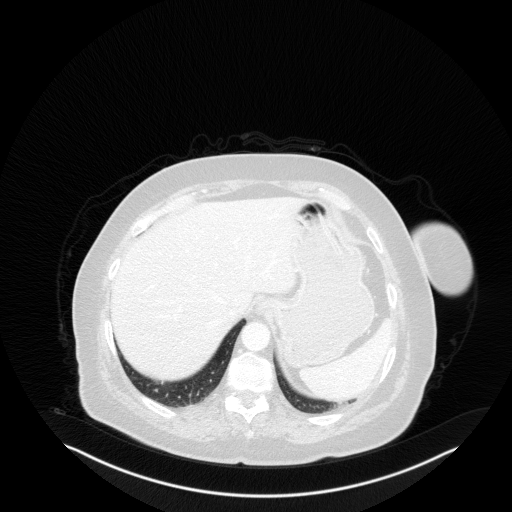

Reconstructed NATIVE CT scan (cycle consistency)

Full window (WL 1023.5, WW 4095 β†’ Low βˆ’1024, High +3071)

Lung window (WL -600, WW 1500 β†’ Low βˆ’1350, High +150)